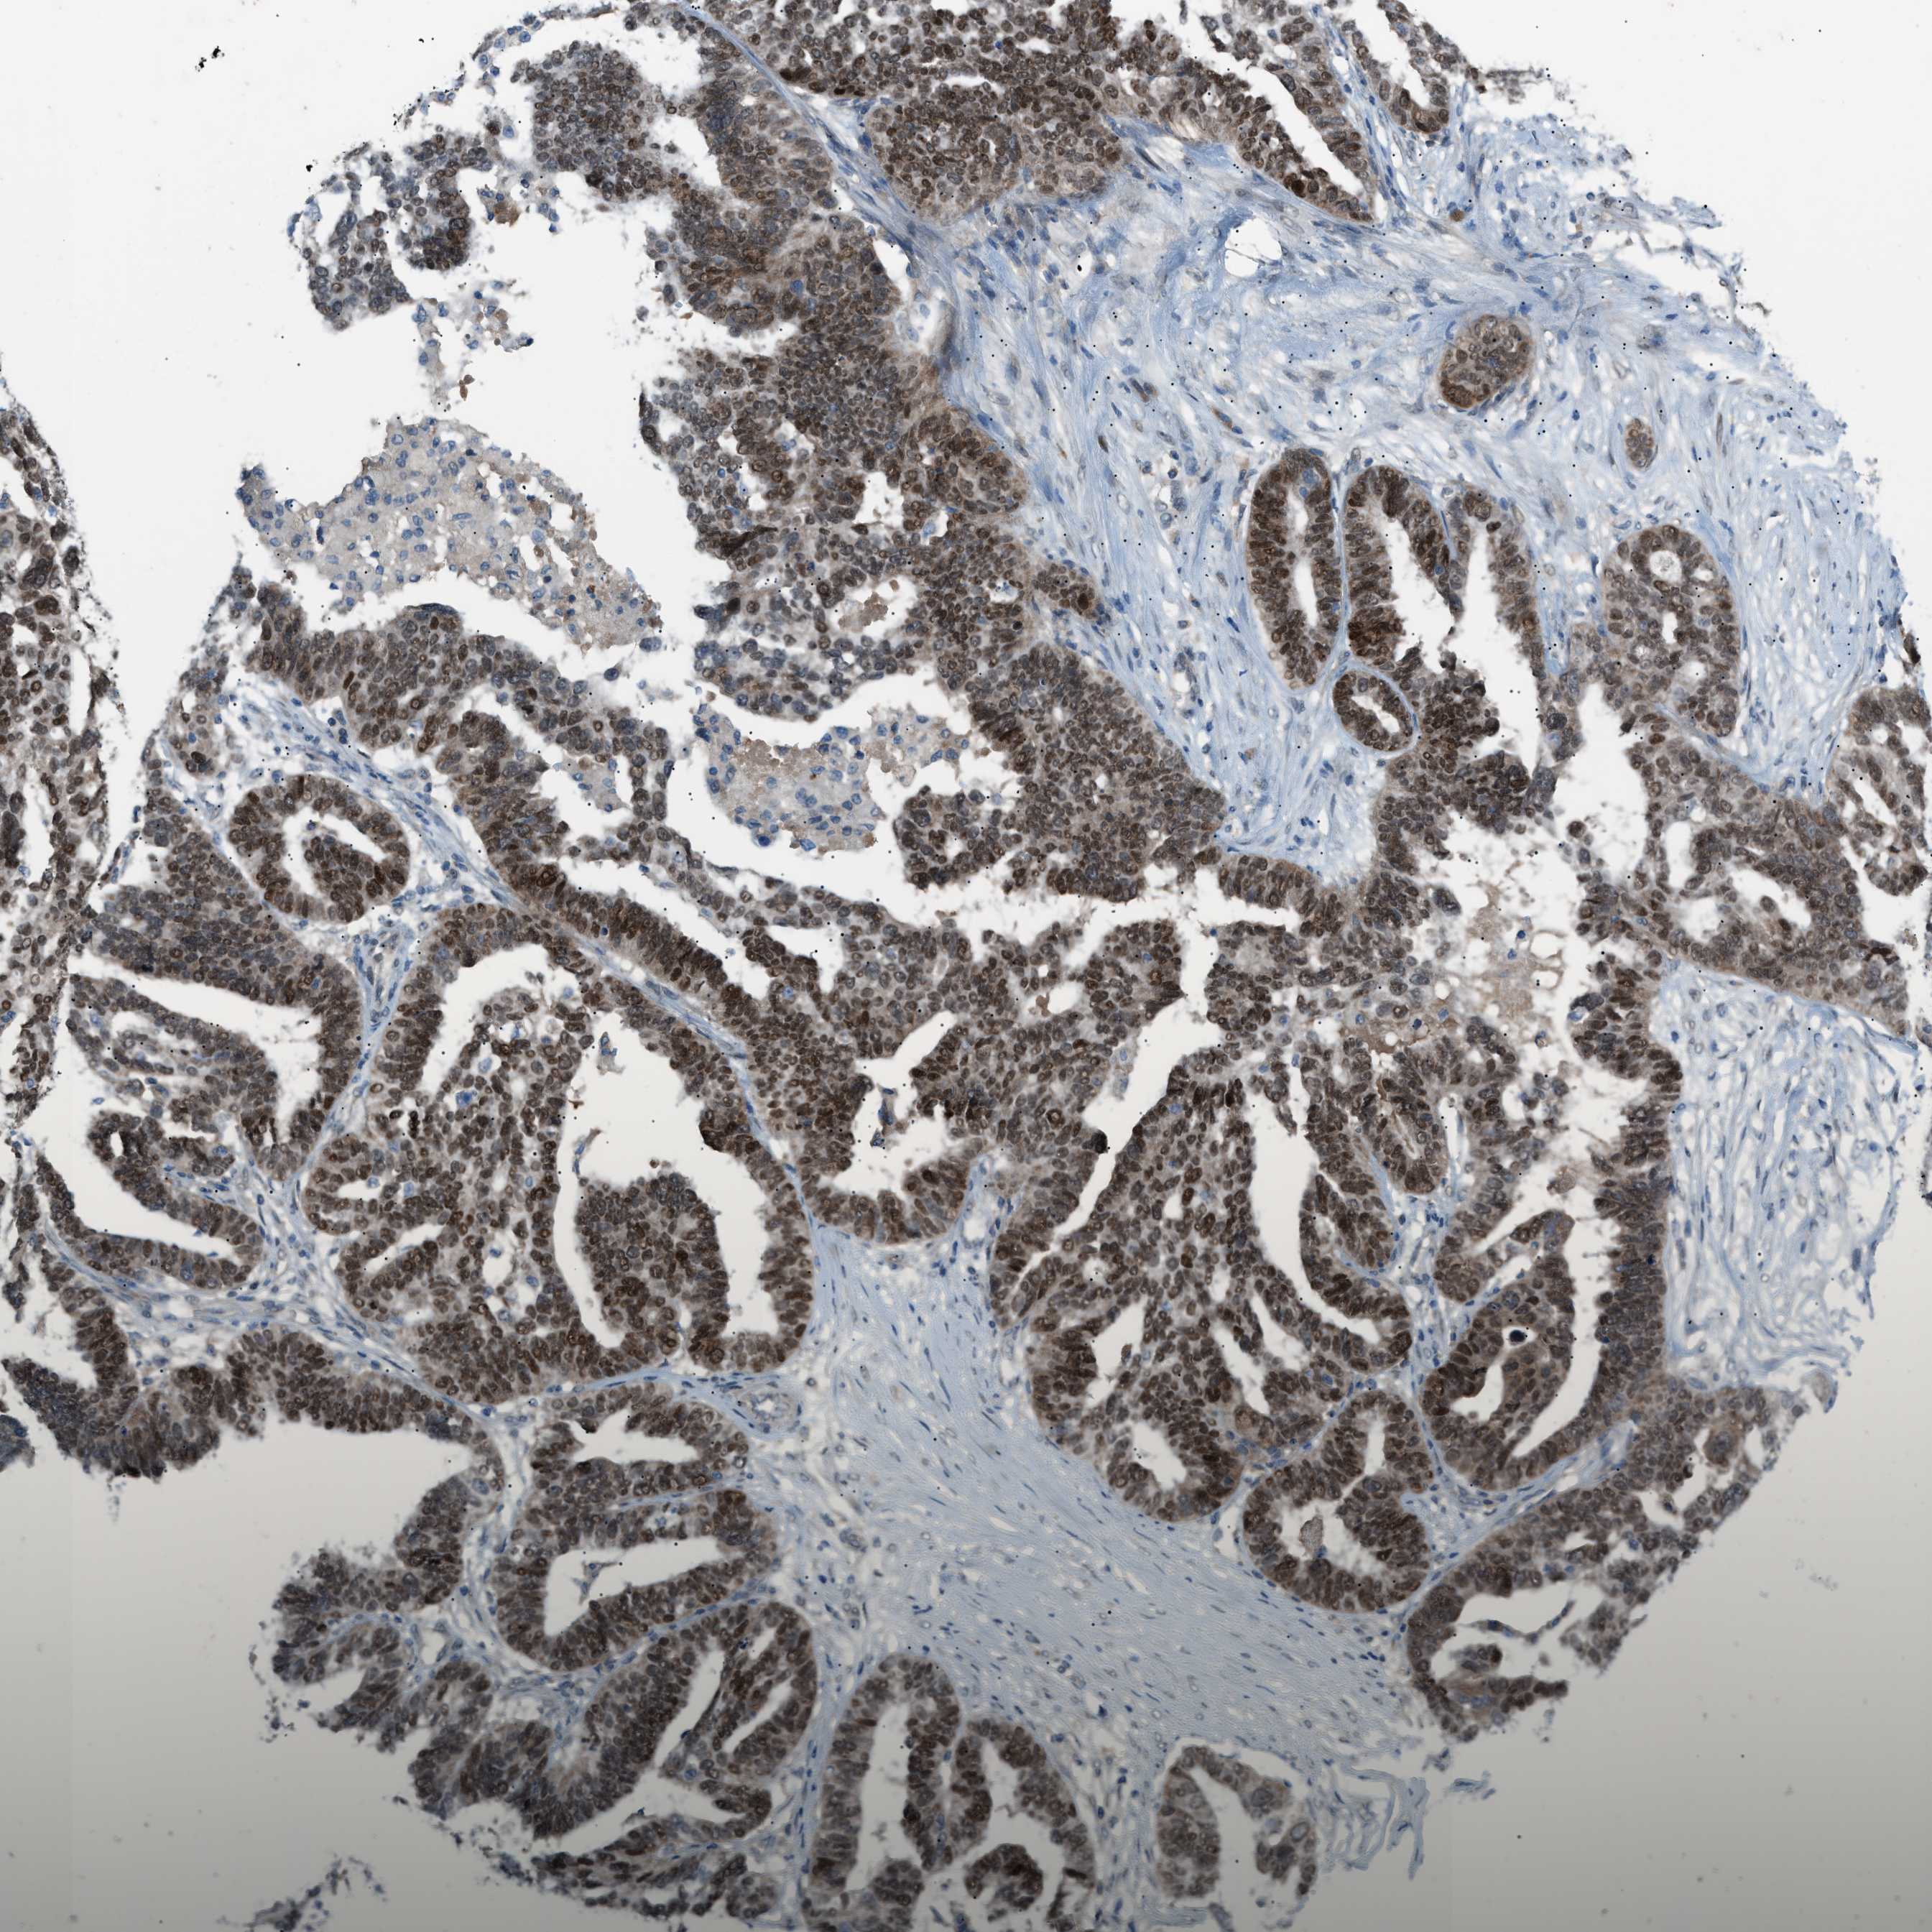

OVARIAN CANCER - Protein expressioni

A mouse-over function shows sample information and annotation data. Click on an image to view it in a full screen mode. Samples can be filtered based on level of antibody staining by selecting one or several of the following categories: high, medium, low and not detected. The assay and annotation is described here.

Note that samples used for immunohistochemistry by the Human Protein Atlas do not correspond to samples in the TCGA dataset.

Antibody stainingi

Antibody staining in the annotated cell types in the current human tissue is reported as not detected, low, medium, or high, based on conventional immunohistochemistry profiling in selected tissues. This score is based on the combination of the staining intensity and fraction of stained cells.

Each image is clickable and will lead to virtual microscopy that enables deeper exploration of all samples and also displays staining intensity scores, fraction scores and subcellular localization as well as patient and tissue information for each sample.

Antibody HPA015323

Antibody HPA015810

Cystadenocarcinoma, serous, NOS